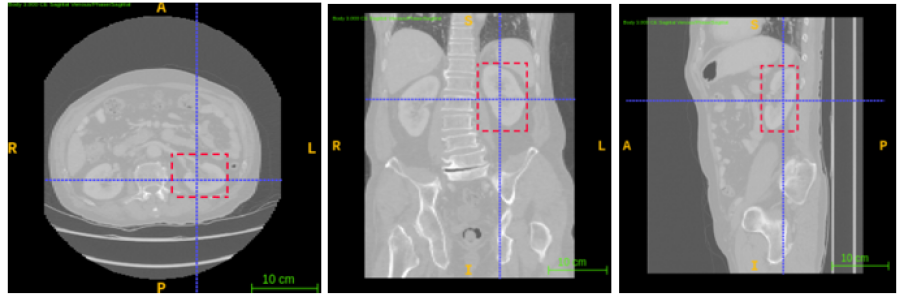

3.2.2 Annotation

The annotation process using ITK-SNAP in the three planes is illustrated in Fig 1 for creating a 3D bounding box around a lumbar spine region. The annotations of spleen, left and right kidneys are illustrated by Figures 2, 3 and 4 respectively.

The dataset was provided by the Prince of Wales Hospital, Randwick, NSW, Australia in an anonymised form after ethics approval (refer 3.1), and included 110 abdomen CT scans with a slice thickness of 3mm for lumbar spine and left kidney and 104 scans for spleen and right kidney localisation. The data set was manually annotated and verified by a radiologist with 10 years of experience, to identify the two diagonally opposite corner points of a 3D bounding box around the ROI. Annotations were performed to localise left and right kidneys using ITK-SNAP as described in section 3.2.2.